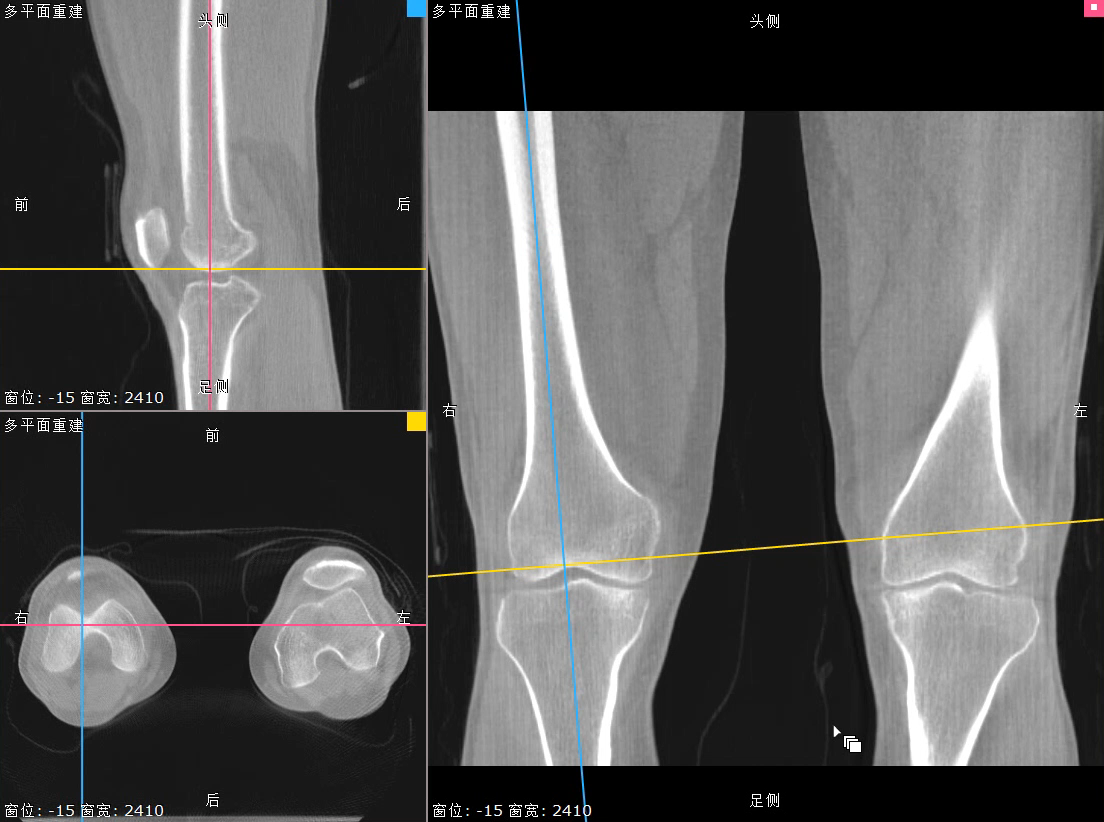

对于WR-3D技术的问世,主要解决了两大核心问题:1、解决了普放DR漏诊率高的现状,常规DR设备仅有某一角度的二维影像、密度信息极差,而WR-3D能获得更丰富的诊断信息,多角度拍摄三维重建影像,任意角度任意切面以及高敏感的密度信息;2、解决了CT无法获得立位(负重位)的三维影像,WR-3D无论是在断层图像重建、MPR多平面重建、VR体绘制都有着优异的表现,而对于临床诊断尤其是骨科,负重位的影像更具有临床价值。患者在负重位状态下肌肉状态、关节间隙及骨骼力线等都与患者平躺时是明显不同的。因此WR-3D在术前精准规划与术后精准评估方面有其非常重要的临床价值。

负重位状态下WR-3D MPR多平面重建